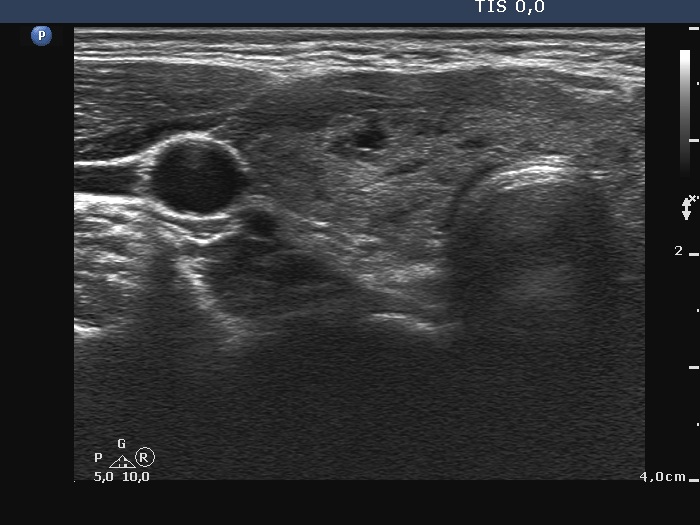

First examination (first row of images)

Clinical presentation: A 20-yr-old woman was referred for ultrasound examination. An elevated aTPO level was detected on evaluation of dysmenorrhea.

Palpation: Both lobes were firm. The left lobe was suspicious having a nodule.

Laboratory tests: TSH 2.08 mIU/L, FT4 13.2 pM/L, aTPO > 1300 U/mL.

The dimensions of the nodule in the left lobe were 18x17x22 mm, width, depth, length, respectively, the volume of the lesion was 3.5 mL.

The patient did not consent to aspiration cytology.